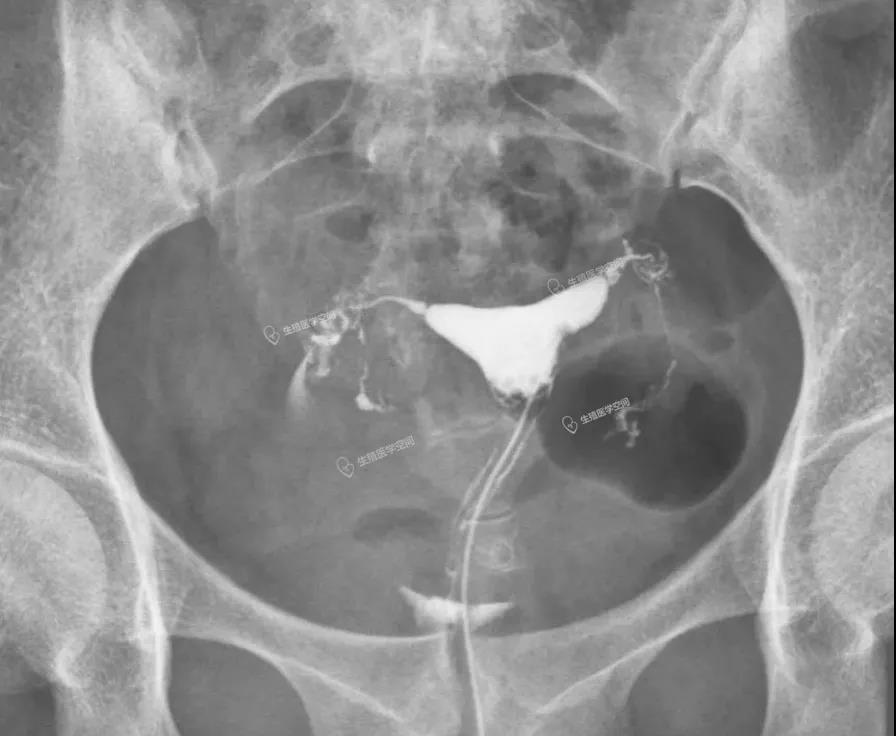

病例2 女 32岁 继发不孕,子宫输卵管造影发现双侧输卵管峡部阻塞,为峡部结节性输卵管炎(SIN)所致输卵管闭塞,不管是宫腹腔镜或放射科的介入再通术都疏通不成功。男方检查均正常。于是做试管婴儿。足月顺产一健康婴儿。